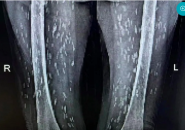

Nghiện Món Vạn Người Mê, Cụ Bà Bị Kén Sán Ken Đặc Khắp Cơ Thể

Đi kiểm tra sức khoẻ, cụ bà choáng váng khi trên phim X- quang kén sán như hạt gạo ken đặc khắp cơ thể.